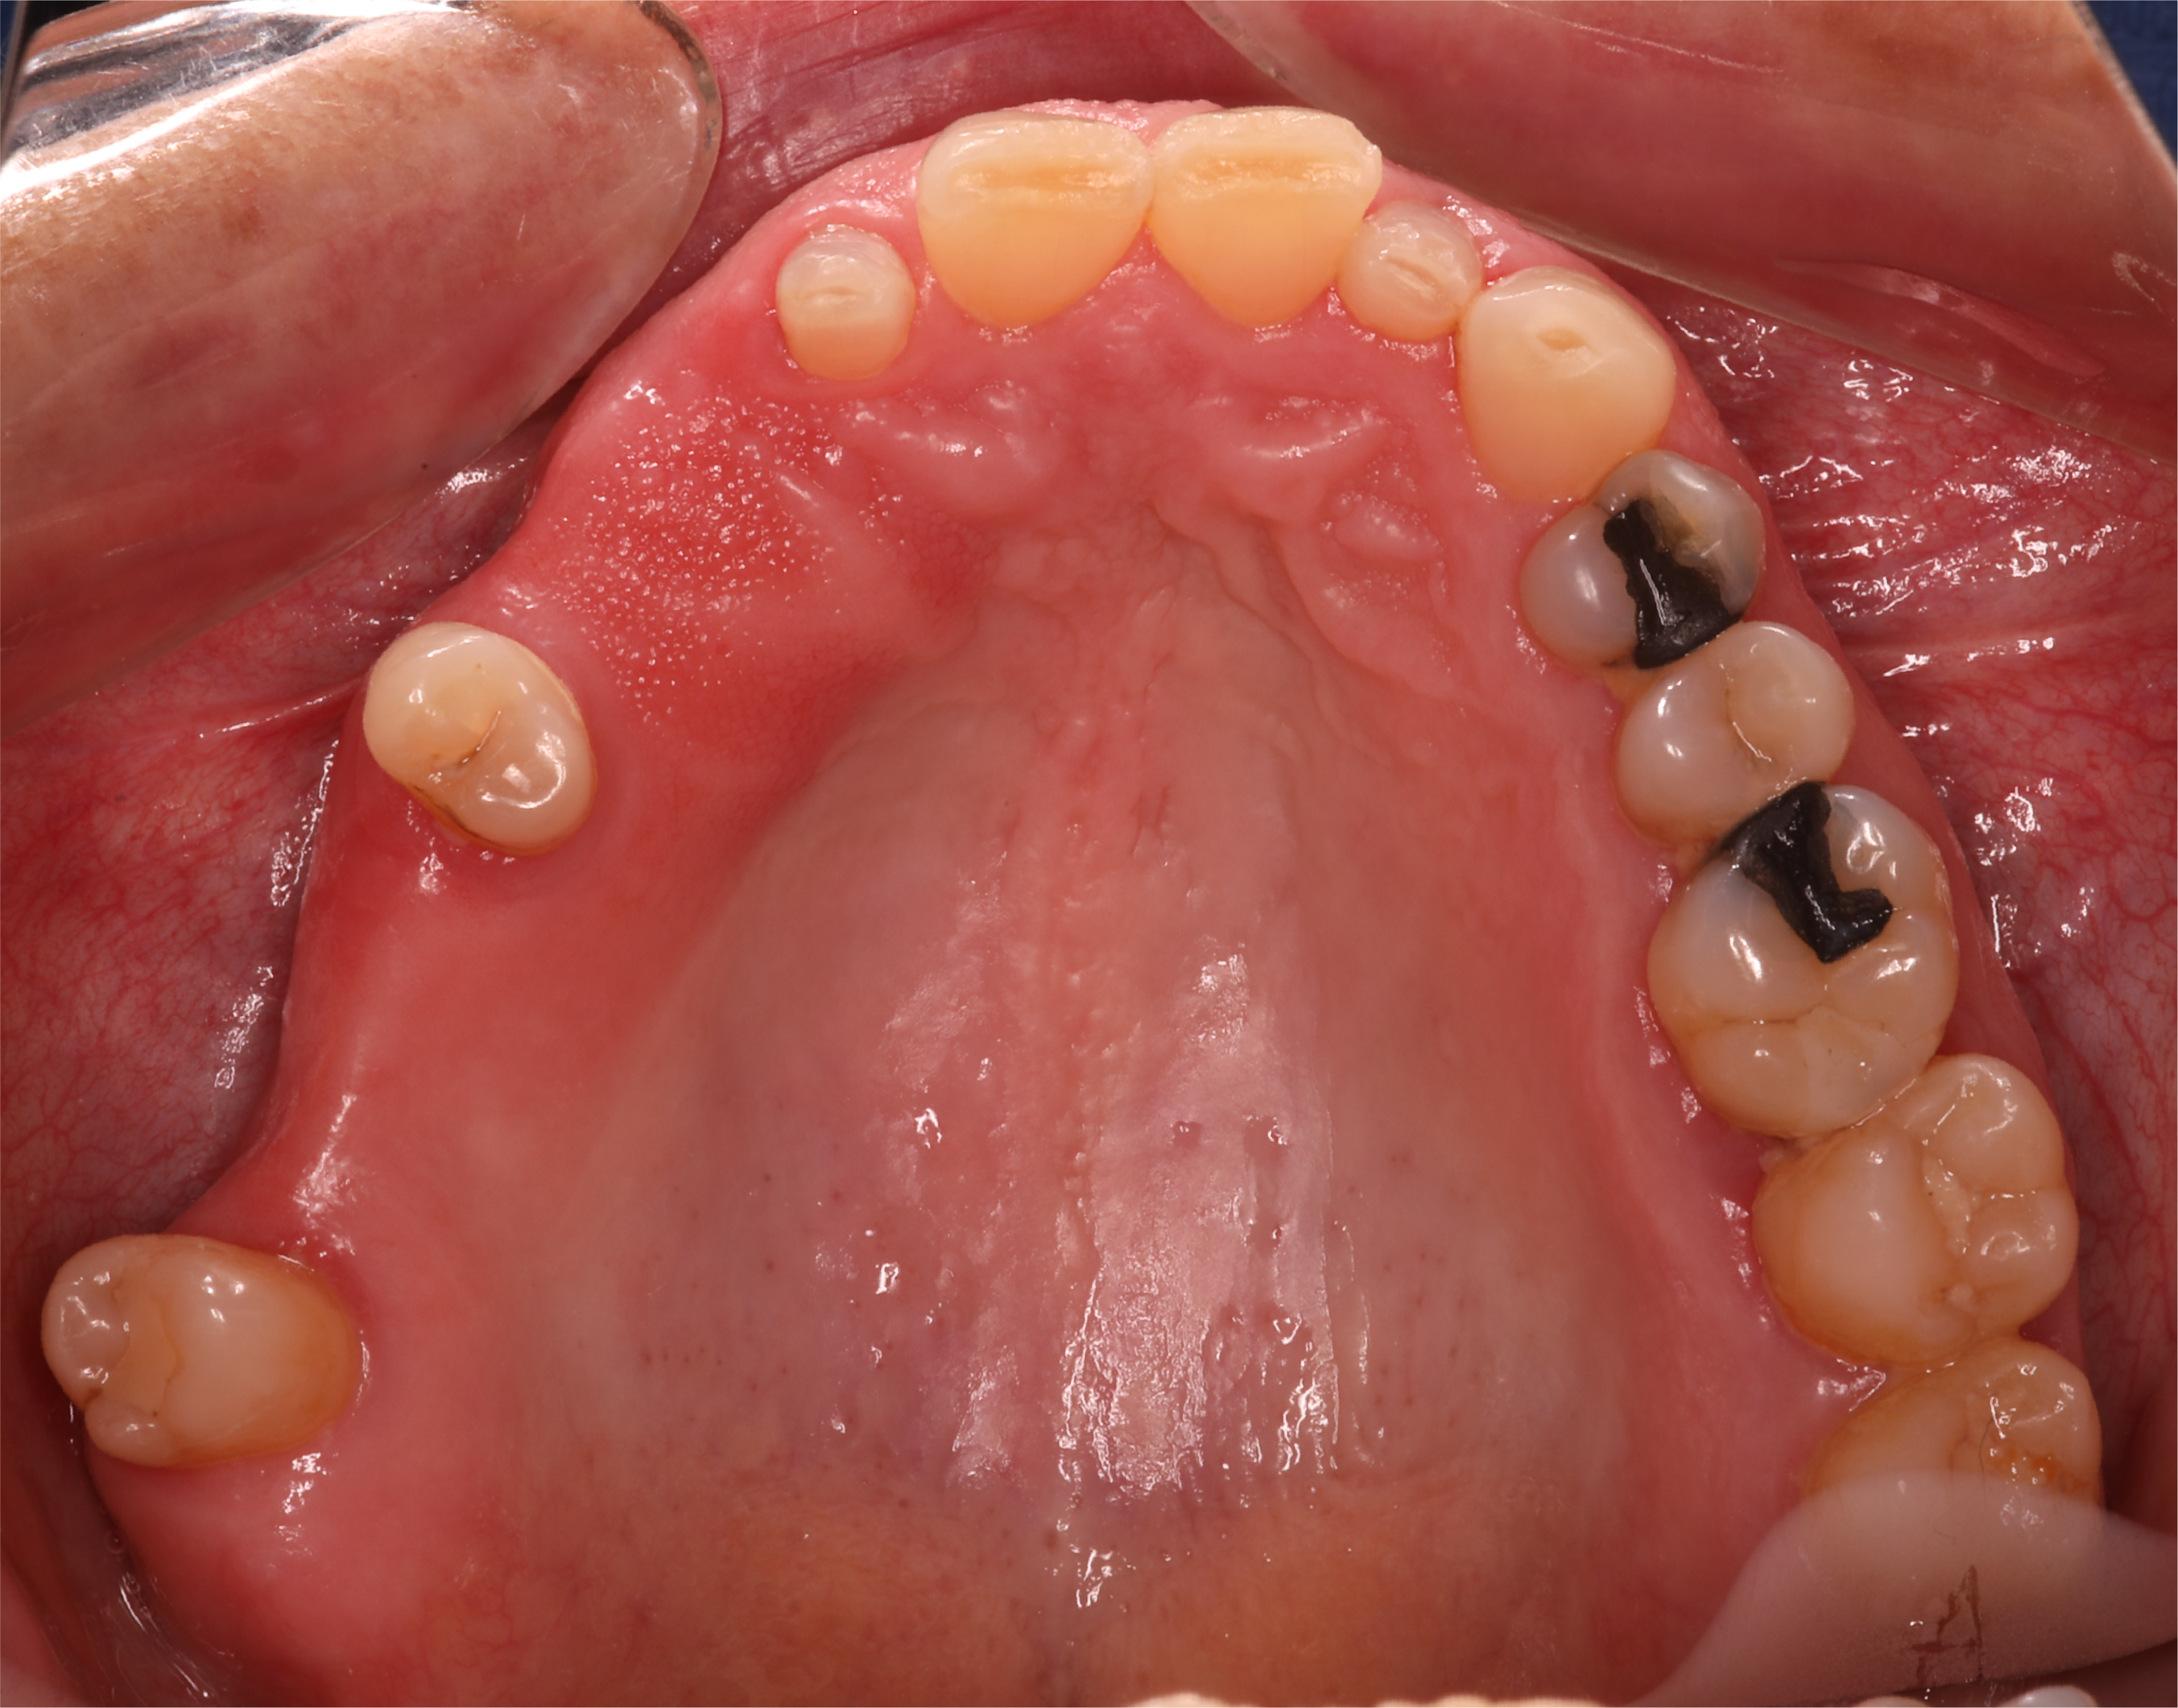

Sorriso da paciente antes de iniciar qualquer tratamento.